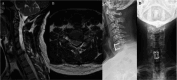

Figures